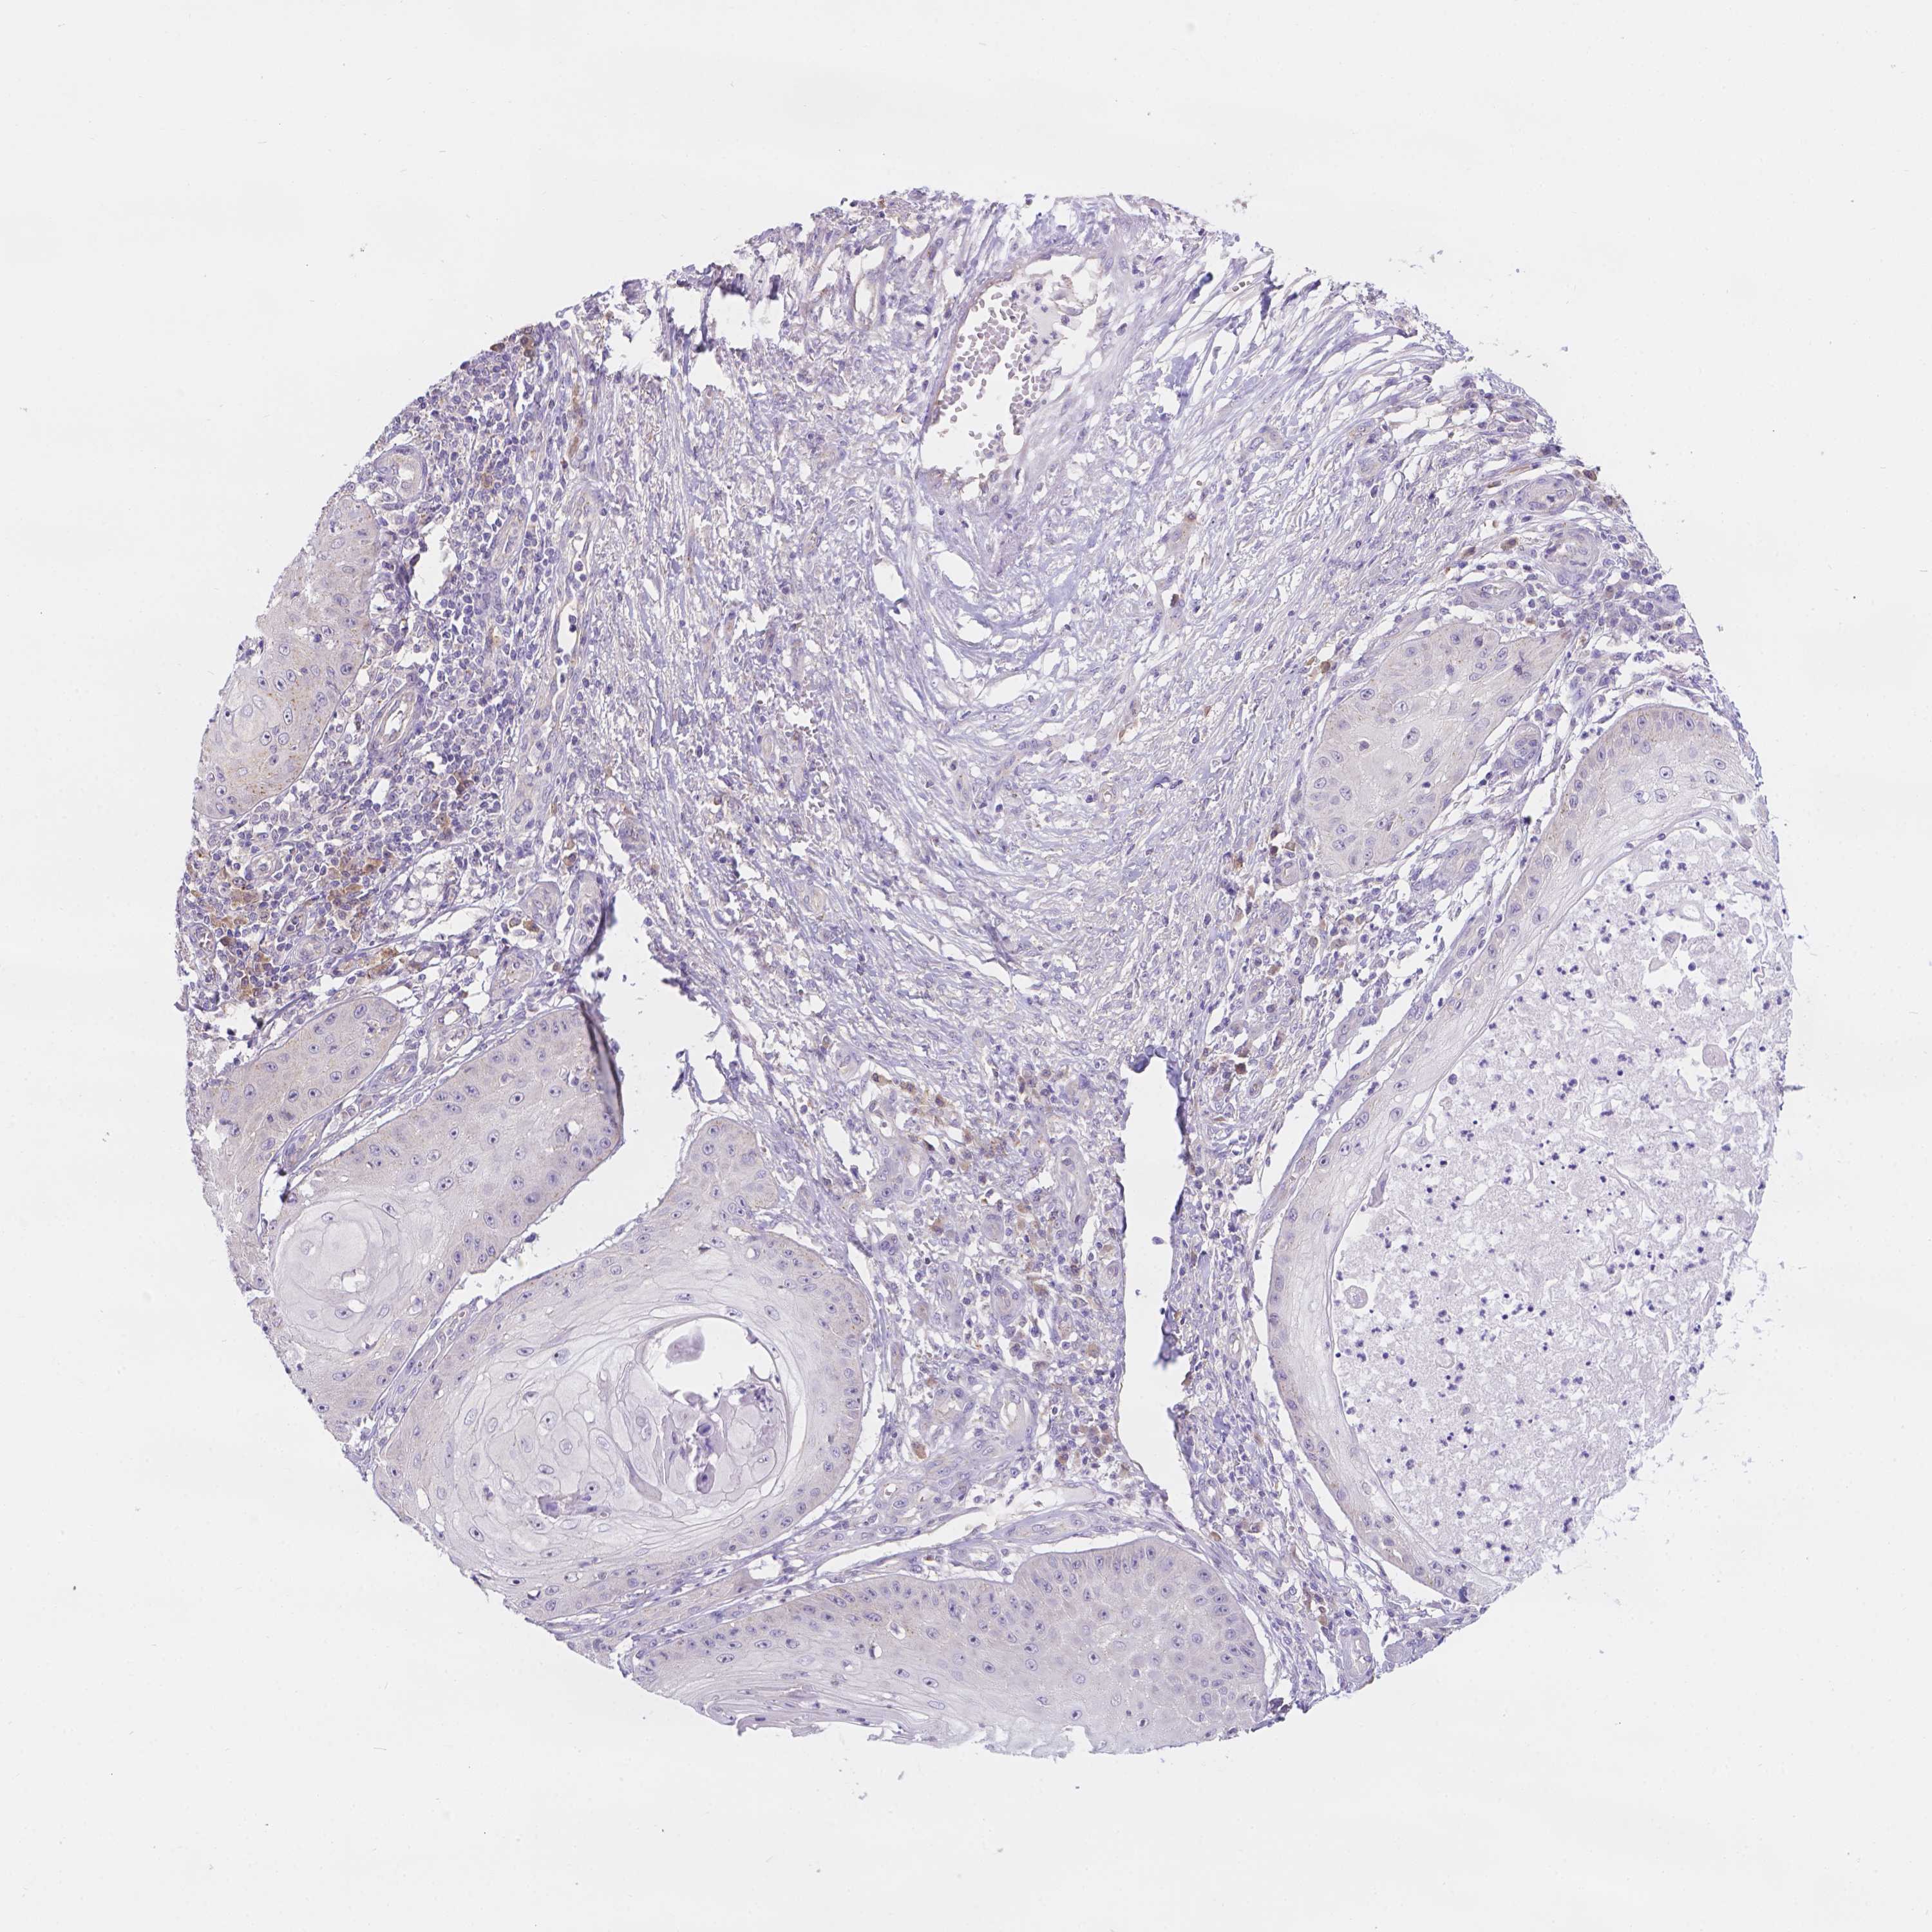

Basal cell and squamous cell cancer

SKIN CANCER - Protein expressioni

A mouse-over function shows sample information and annotation data. Click on an image to view it in a full screen mode. Samples can be filtered based on level of antibody staining by selecting one or several of the following categories: high, medium, low and not detected. The assay and annotation is described here.

Each image is clickable and will lead to virtual microscopy that enables deeper exploration of all samples and also displays staining intensity scores, fraction scores and subcellular localization as well as patient and tissue information for each sample.

Antibody HPA066754

Basal cell carcinoma

Squamous cell carcinoma, NOS